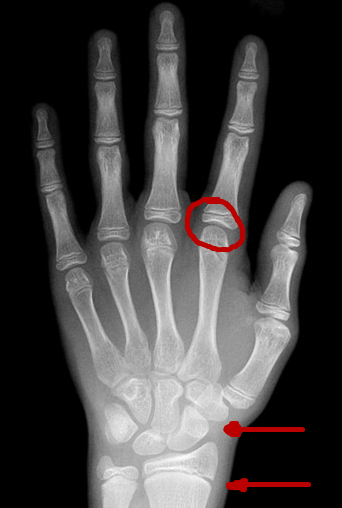

那我们怎么知道骨骺是否闭合了呢?可以通过骨龄来判断,通常来讲就是骨头的年龄,但是骨龄不一定等于一个时期的年龄。骨龄可以通过拍摄手掌骨的X片,一般拍的是左手,可以了解腕骨和掌骨的发育情况。

男孩6岁

男孩14岁

这是一个骨龄的片子,孩子身高不能够掉以轻心。首先,骨龄它不等于实际年龄,现在高也不意味着成年后一定高。目前男孩的骨龄16岁,女孩的骨龄14岁半基本上骨骺就接近了闭合。男孩骨龄14岁半和女孩骨龄12岁半身高会出现减速,一般来说,身高的年增长会小于2个厘米。身高增长有两个高峰,第一个高峰是0到2岁,出生的时候普遍的均身高是50厘米,第一岁的时候一般是75到76厘米,所以第一年生长大概是25到26个厘米左右,而两岁时可以到85到86厘米。从出生到两岁的整个过程,身高的一个增长速度是35到36个厘米。三岁到青春期间,这是一个生长的稳定期,大概是5到7个厘米每年。第二个生长高峰是在青春期,是性激素的作用开始的标志,如女童一般是乳房出现发育,多在9到14岁的时候,而男童一般是出现睾丸的增大,大部分出现在11到13岁。在这个标志开始以后一到两年会达到身高增长的峰值。整个青春期的生长,男童增长大概是25到30厘米,女童大概是25厘米,大概相当于0到1岁时的增长幅度。